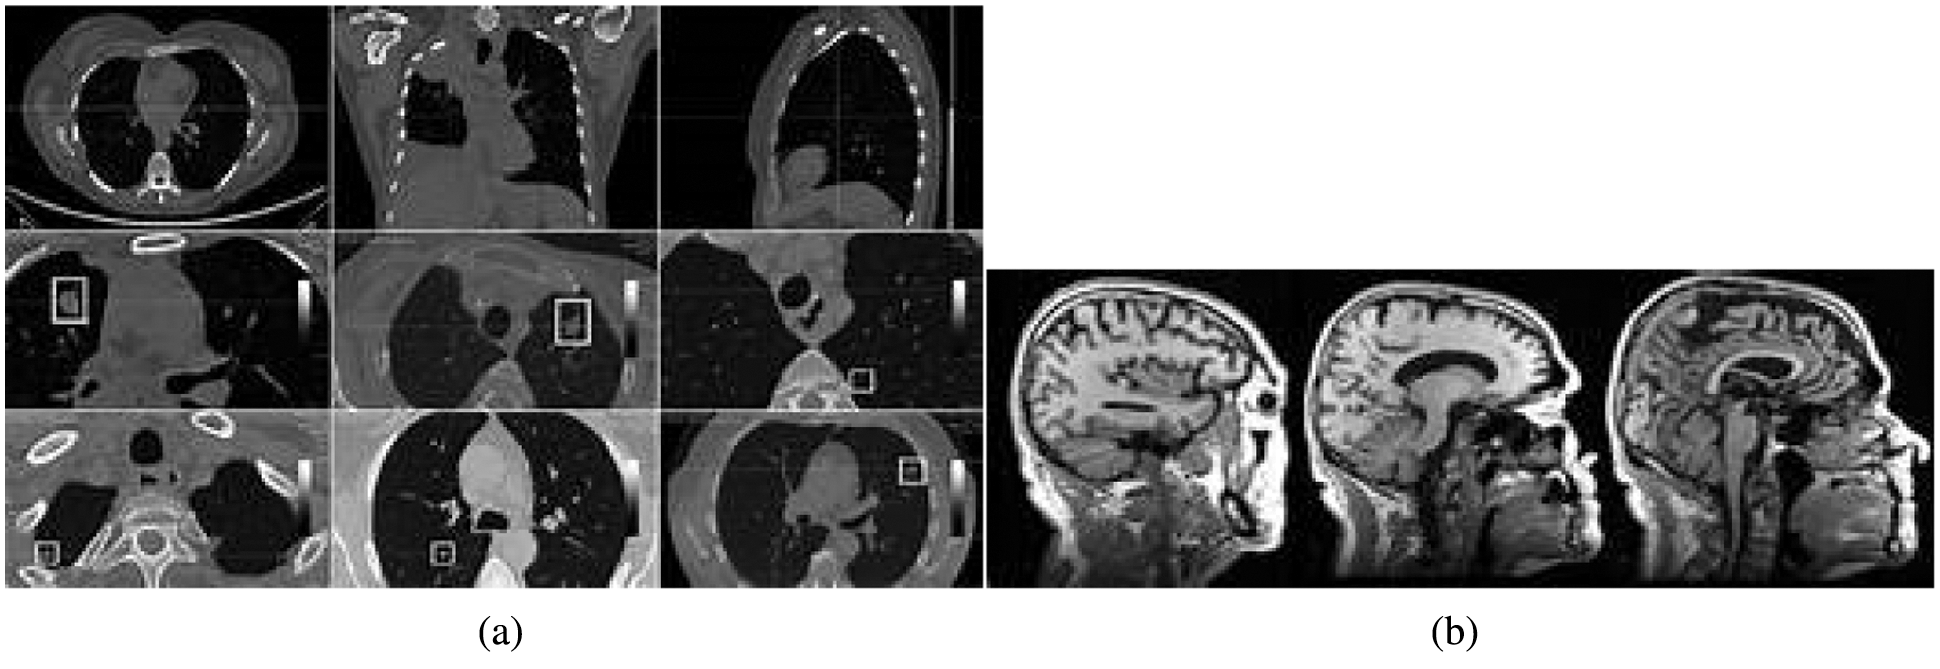

This section discusses the excellent performance of the optimized deep convolution network with the distribution pattern-matching rule (ODCNDPM) algorithm-based medical image analysis process. This work uses different medical images to examine the efficiency of the medical image pattern analysis process. Here, two datasets, namely, the Alzheimer's Disease Neuroimaging Initiative (ADNI) [27] and the ELCAP Public Lung Image Database [28], are utilized to determine the efficiency of the system. The ADNI dataset has 100 brain MRI images utilized to extract the hippocampal regions effectively. The lung dataset consists of 50 low-dose documented lung CT images. The CT scans cover nearly 1.25 mm slice thickness, which helps locate the radiologist's nodules [29]. The discussions present the samples of Alzheimer's disease and lung images in Figs. 4a and 4b.

Figure 4: Sample medical images. (a) ADNI dataset (b) ELCAP public lung image database

From Fig. 4, we can gather any medical images to examine the tumor-affected region. In particular, 80% of the data from the collected regions are utilized for training, and 20% are used for testing. After gathering the medical images, they are processed through the steps above, and the methods are implemented using the uniform platform [34]. Here, NVIDIA GTX1060Ti, Intel i7 Core processors, and MATLAB are utilized to develop the system. A learning rate of 0.001, a batch size of 8, and L2 regularizations of 0.0001 are utilized to segment the affected region during the implementation process. The excellence of the defined system is evaluated using the Dice similarity coefficient (DSC), the predictive positivity value (PPV), and sensitivity metrics. These metrics are used to examine the efficiency of the medical image segmentation process. The values are computed as follows: